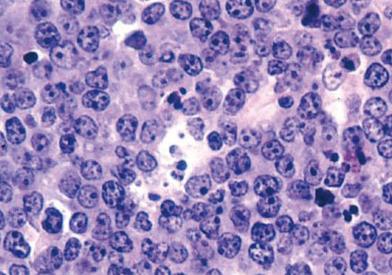

Mantle cell lymphoma is a form of non-Hodgkin B-cell lymphoma. It develops in the mantle cell, a ring of cells within the lymph nodes where B cells—a type of lymphocyte—grow. Most patients with mantle cell lymphoma have an aggressive form of the disease that can spread throughout the bloodstream, digestive system, and bone marrow. Approximately 10-20 percent of patients with mantle cell lymphoma have a slow-growing, non-aggressive version of the disease.

Mantle cell lymphoma occurs when B lymphocytes acquire genetic mutations that alter their function and growth. The most common abnormality, found in 90 percent of cases, causes B lymphocytes to overproduce cyclin D1, a protein that drives the cells’ growth. Other mutations can interfere with B cells’ ability to overcome DNA damage and produce infection-fighting antibodies, leaving patients vulnerable to treatment resistance and long-term complications such as low blood counts and infections.